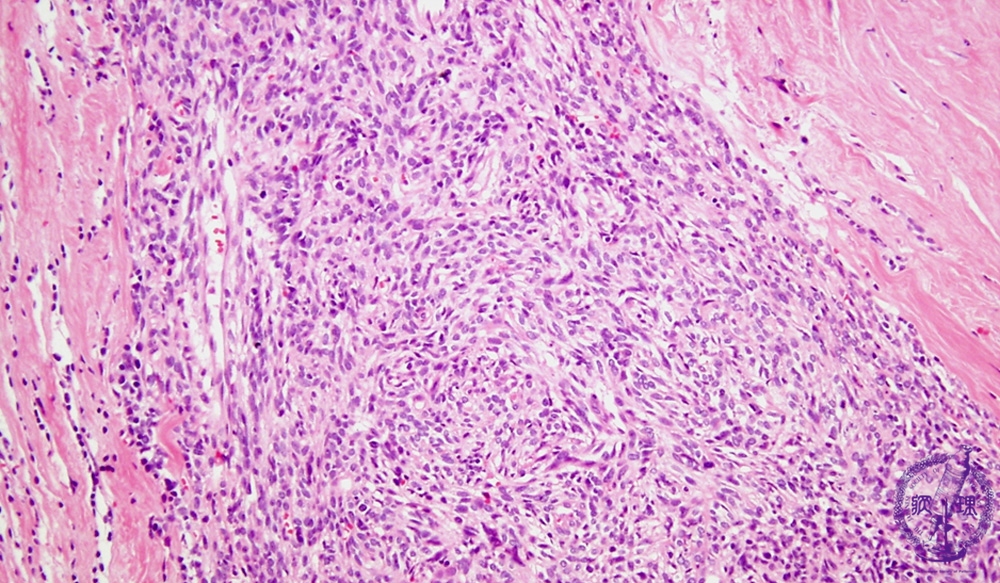

Microscopic view (low power view): WHO (World Health Organization) type A thymoma. WHO type A thymoma is an epithelial neoplasm despite having a mesenchymal appearance demonstrated by spindle cells arranged in a storiform pattern. This subtype has few or no lymphocytes.